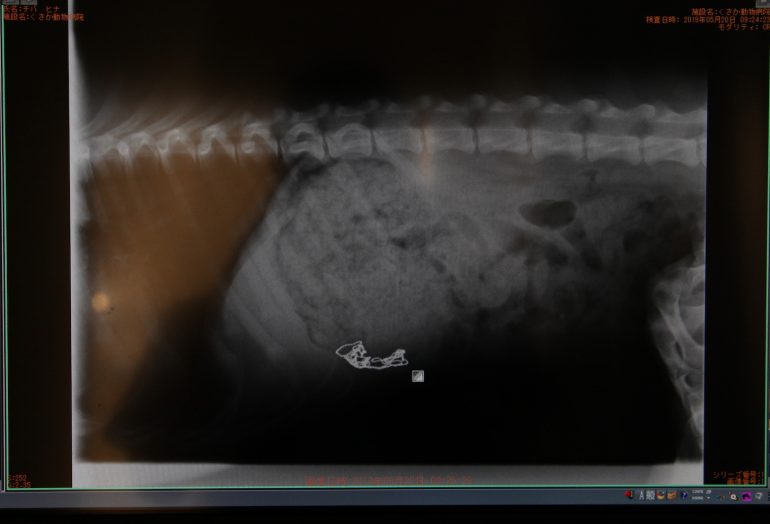

ネックレス 食べちゃった くさか動物病院

オモチャを誤飲した犬の胃切開手術 まだ幼い約5カ月のトイプードルさん。 『子供のオモチャの一部を食べてしまった』とのことで受診。 レントゲンで胃の中に直径15cm程度の異物を確認し、オーナー様が持参した同一異物の大きさ、形状から手術する. 犬のレントゲン検査とは レントゲン検査は「X線検査」とも呼ばれているもので、X線を使って体内の様子を外側から調べる検査です。 この検査で対象となるのは、「胸部」「腹部」「運動器」(特に骨)など全身にわたります。 レントゲンには実際のレントゲンフィルム(写真のように現像を必要とするもの)とデジタル画像(フィルムは使わずモニター等で見る. 対象ペット:犬 / ゴールデンレトリバー / 女の子 / 6歳 8ヵ月 36 今年一月頃右肋骨付近に硬いコリコリしたものを みつけた。3月に病院受診、レントゲンをとってもらったけど何も映らな.